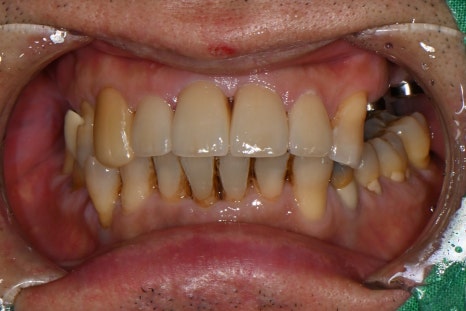

🖼️ Lip trauma photo / Front tooth fracture and fixation photo / X-ray photo

Lip laceration immediately after the trauma / Initial emergency treatment photo showing fixation of the dislocated front tooth

They had fallen, causing a deep cut to the lip and trauma in which the front tooth broke and became loose.

6 cm penetrating laceration on the outer lip, 4 cm on the inner lip

Multiple upper front teeth dislocated and loosened